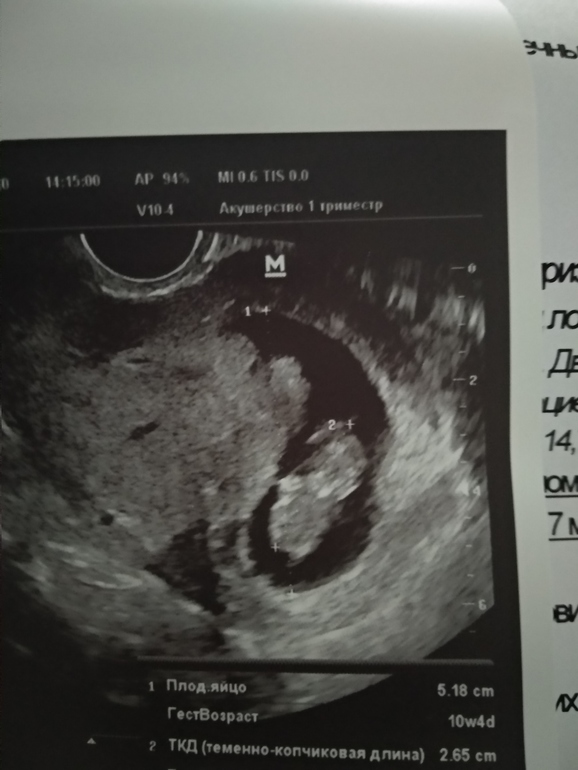

Вопросы про УЗИ, обследования и анализы: что, где, как, когда?Сходила сегодня на 2 узи за все время. С малышом все хорошо, Слава Богу!!! Ктр - 26.5 мм, ЧСС -166, движения плода "+", жм -4.5 мм, Пя- 51,8 мм. Прикреплен по задней стенке. Лежал спинкой. Но!!! Врач на узи увидела выше плода, ближе к верхней стенке матки гетерогенное образование размером 33*23мм. Довольно большое, там есть какое-то движение. Врач - к.м.н!!! Она сказала, она впервые такое видит, не знает что это. Сказала идти в жк, чтоб там дали направление в перинат.центр. Ребенок вырос, даже почти догнали срок по М. На прошлом узи по М было 8 н, по ктр поставили 7н, сегодня 10 недель, по ктр 9.3. Она сказала, что плоду не мешает развиваться, но что это? Прочитала в интернете, что бывает амниотич.киста. Я ее спросила, если они оба в Пя, может это второй, не развивается, она сказала, что нет.

вот это, внутри жидкость, есть движение.

Это слева малыш, справа образование, оно прилегает вплотную к ЖМ.